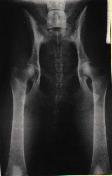

Pro objektivní posouzení DKK by měl být snímek

symetrický, jelikož špatně zhotovený snímek může vést k chybné

interpretaci nálezu. Na snímku by tedy měla být zachycena celá pánev,

kost křížová a obě stehenní kosti včetně kolenních kloubů, pouze u

velkých a obřích plemen je dovoleno posunout pánev tak, že na snímku

nejsou vidět obě pately (čéšky). Stehenní kosti by měly probíhat

rovnoběžně mezi sebou a součastně s podélnou osou těla.

ŠPATNĚ PROVEDENÝ RTG SNÍMEK!!

Projekce není symetrická - stehenní kosti a podélná

osa těla nejsou rovnoběžné. |

Dále by se měla věnovat velká pozornost projekčně

dokonalému snímku. Jakékoli nevyhovující kvalita snímku může poté opět

negativně ovlivnit konečné hodnocení snímku, zejména v případě

hraničních stupňů dysplazie.

Na levém snímku můžeme vidět kyčelní klouby zdravého

zvířete, ale na druhém snímku je zrentgenované zvíře postižené těžkou

dysplazií.